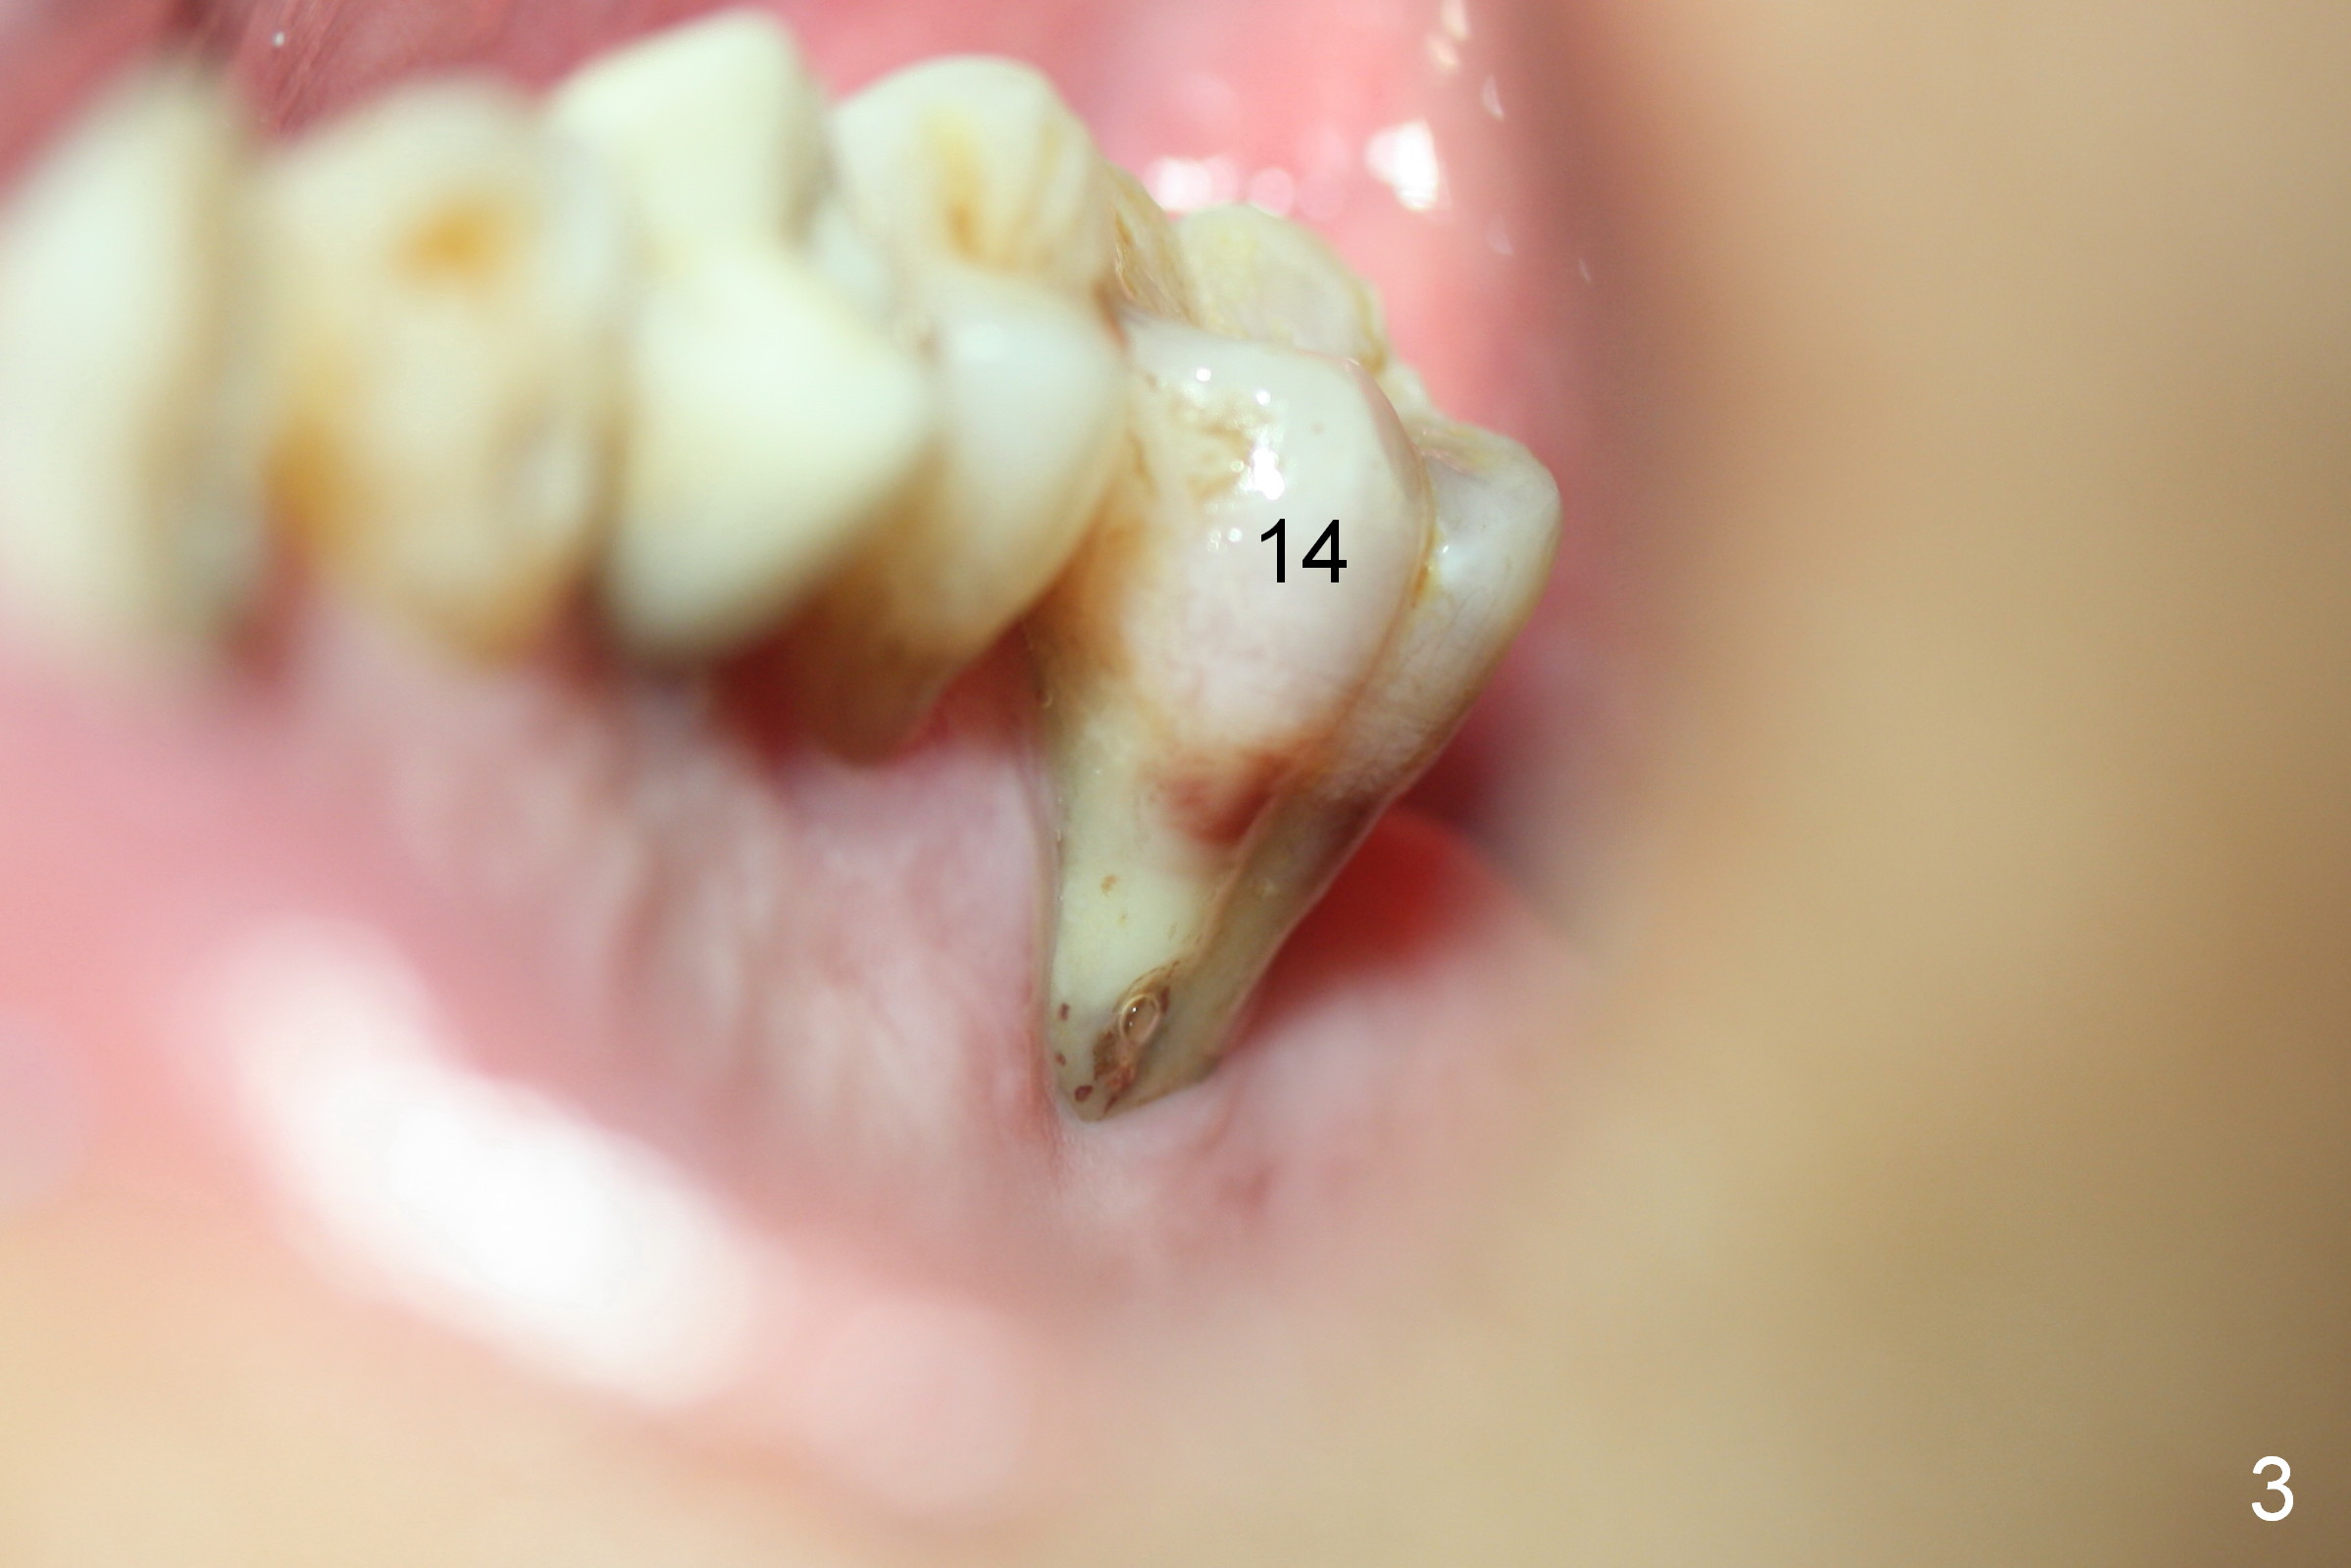

A 52-year-old man (DM) will return for #14 extraction and immediate implant nearly 2 years after #12 crown cementation. There is more bone loss distally than mesially. Clinically, the palatal recession is excessive (Fig.3). After socket debridement and 2% Xylocaine/1:50,000 Epinephrine gauze packing, osteotomy will be initiated in the buccomesial aspect of the septum, if the latter is present. Use 4.5 or 5x17 mm tap to test stability and more importantly determine how much thread exposure can occur palatally before placing a 14 or 17 mm long implant (Fig.2). A fair amount of bone graft will be inserted distopalatally (red circles in Fig.2). If primary stability is achieved, use an immediate provisional to close the socket opening.